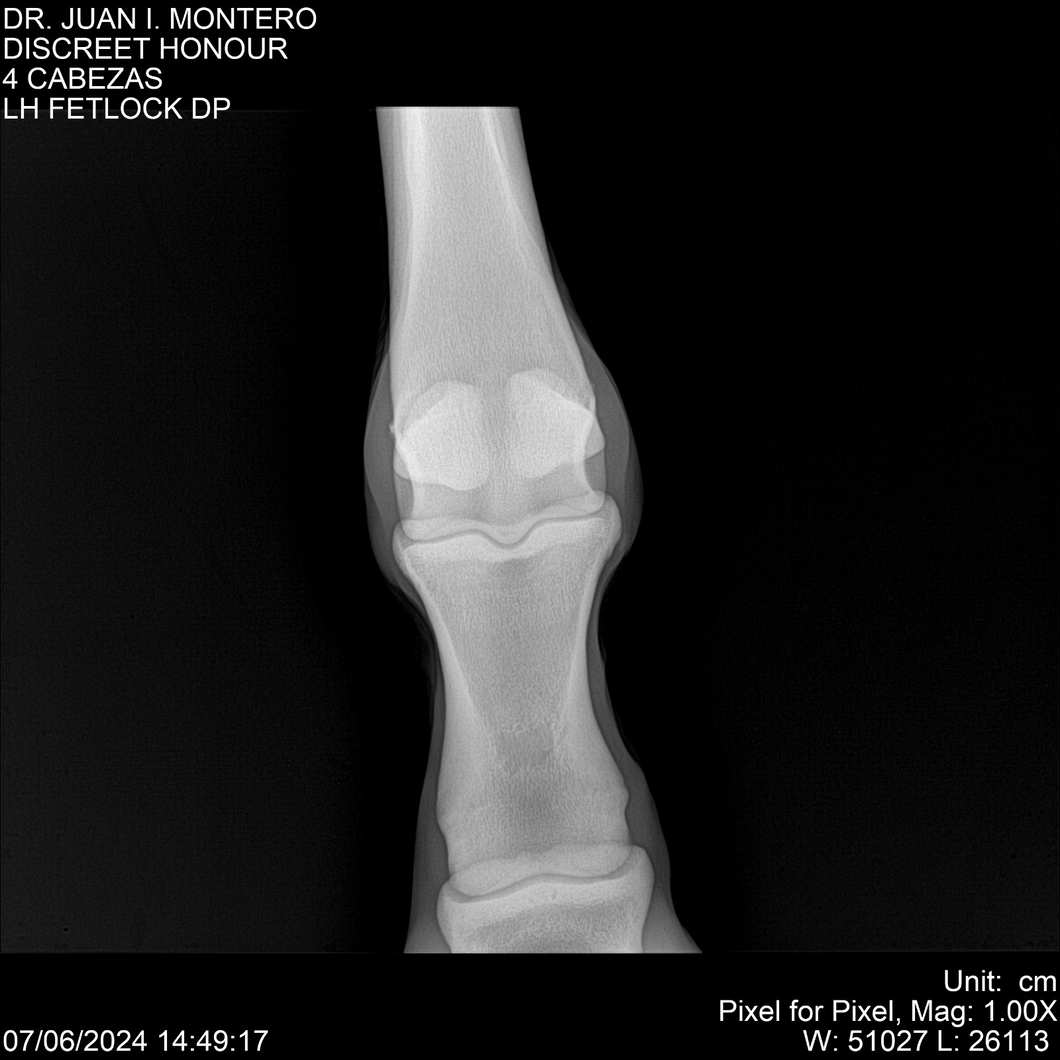

LOTE 6, DISCREET HONOUR 🔥 🔥 🔥 Lote Anterior Volver al remate Lote Siguiente Ficha Contacto Montevideo - Ficha del Lote Identificador: #281093 Categoría: Yeguarizos Montevideo - 82 Visualizaciones ClicData Contacto Empresa: Abelenda N. R., Walter Hugo Nombre*: Teléfono* : E-mail* : Mensaje Enviar Registrese gratis Este contenido Exclusivo está disponible sólo para usuarios registrados Ingresar